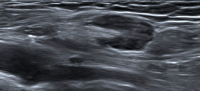

Abbildung 4: Fehlende Gleichmäßigkeit des Lymphknotenkortex. Besonders am rechten Rand des Lymphknotens fällt die exzentrische Verbreiterung des Kortex auf. Hodgkin-Lymphom-Rezidiv.